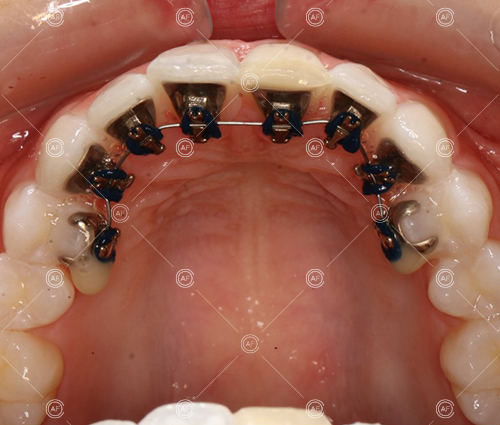

Residual space from the extractions were closed using upper and lower nickel titanium closing coils. Class 2 elastics were used to facilitate space closure in order to gain class 1 buccal segments.

MH debonded in December 2020, with overall treatment time of around 14 months.

She was provided with upper and lower vacuum form retainers, and asked to wear these every night for the first year, and alternate nights for the second year onwards, indefinitely for as long as she wanted her teeth to remain straight. High quality finish was maintained at one year post-debond.